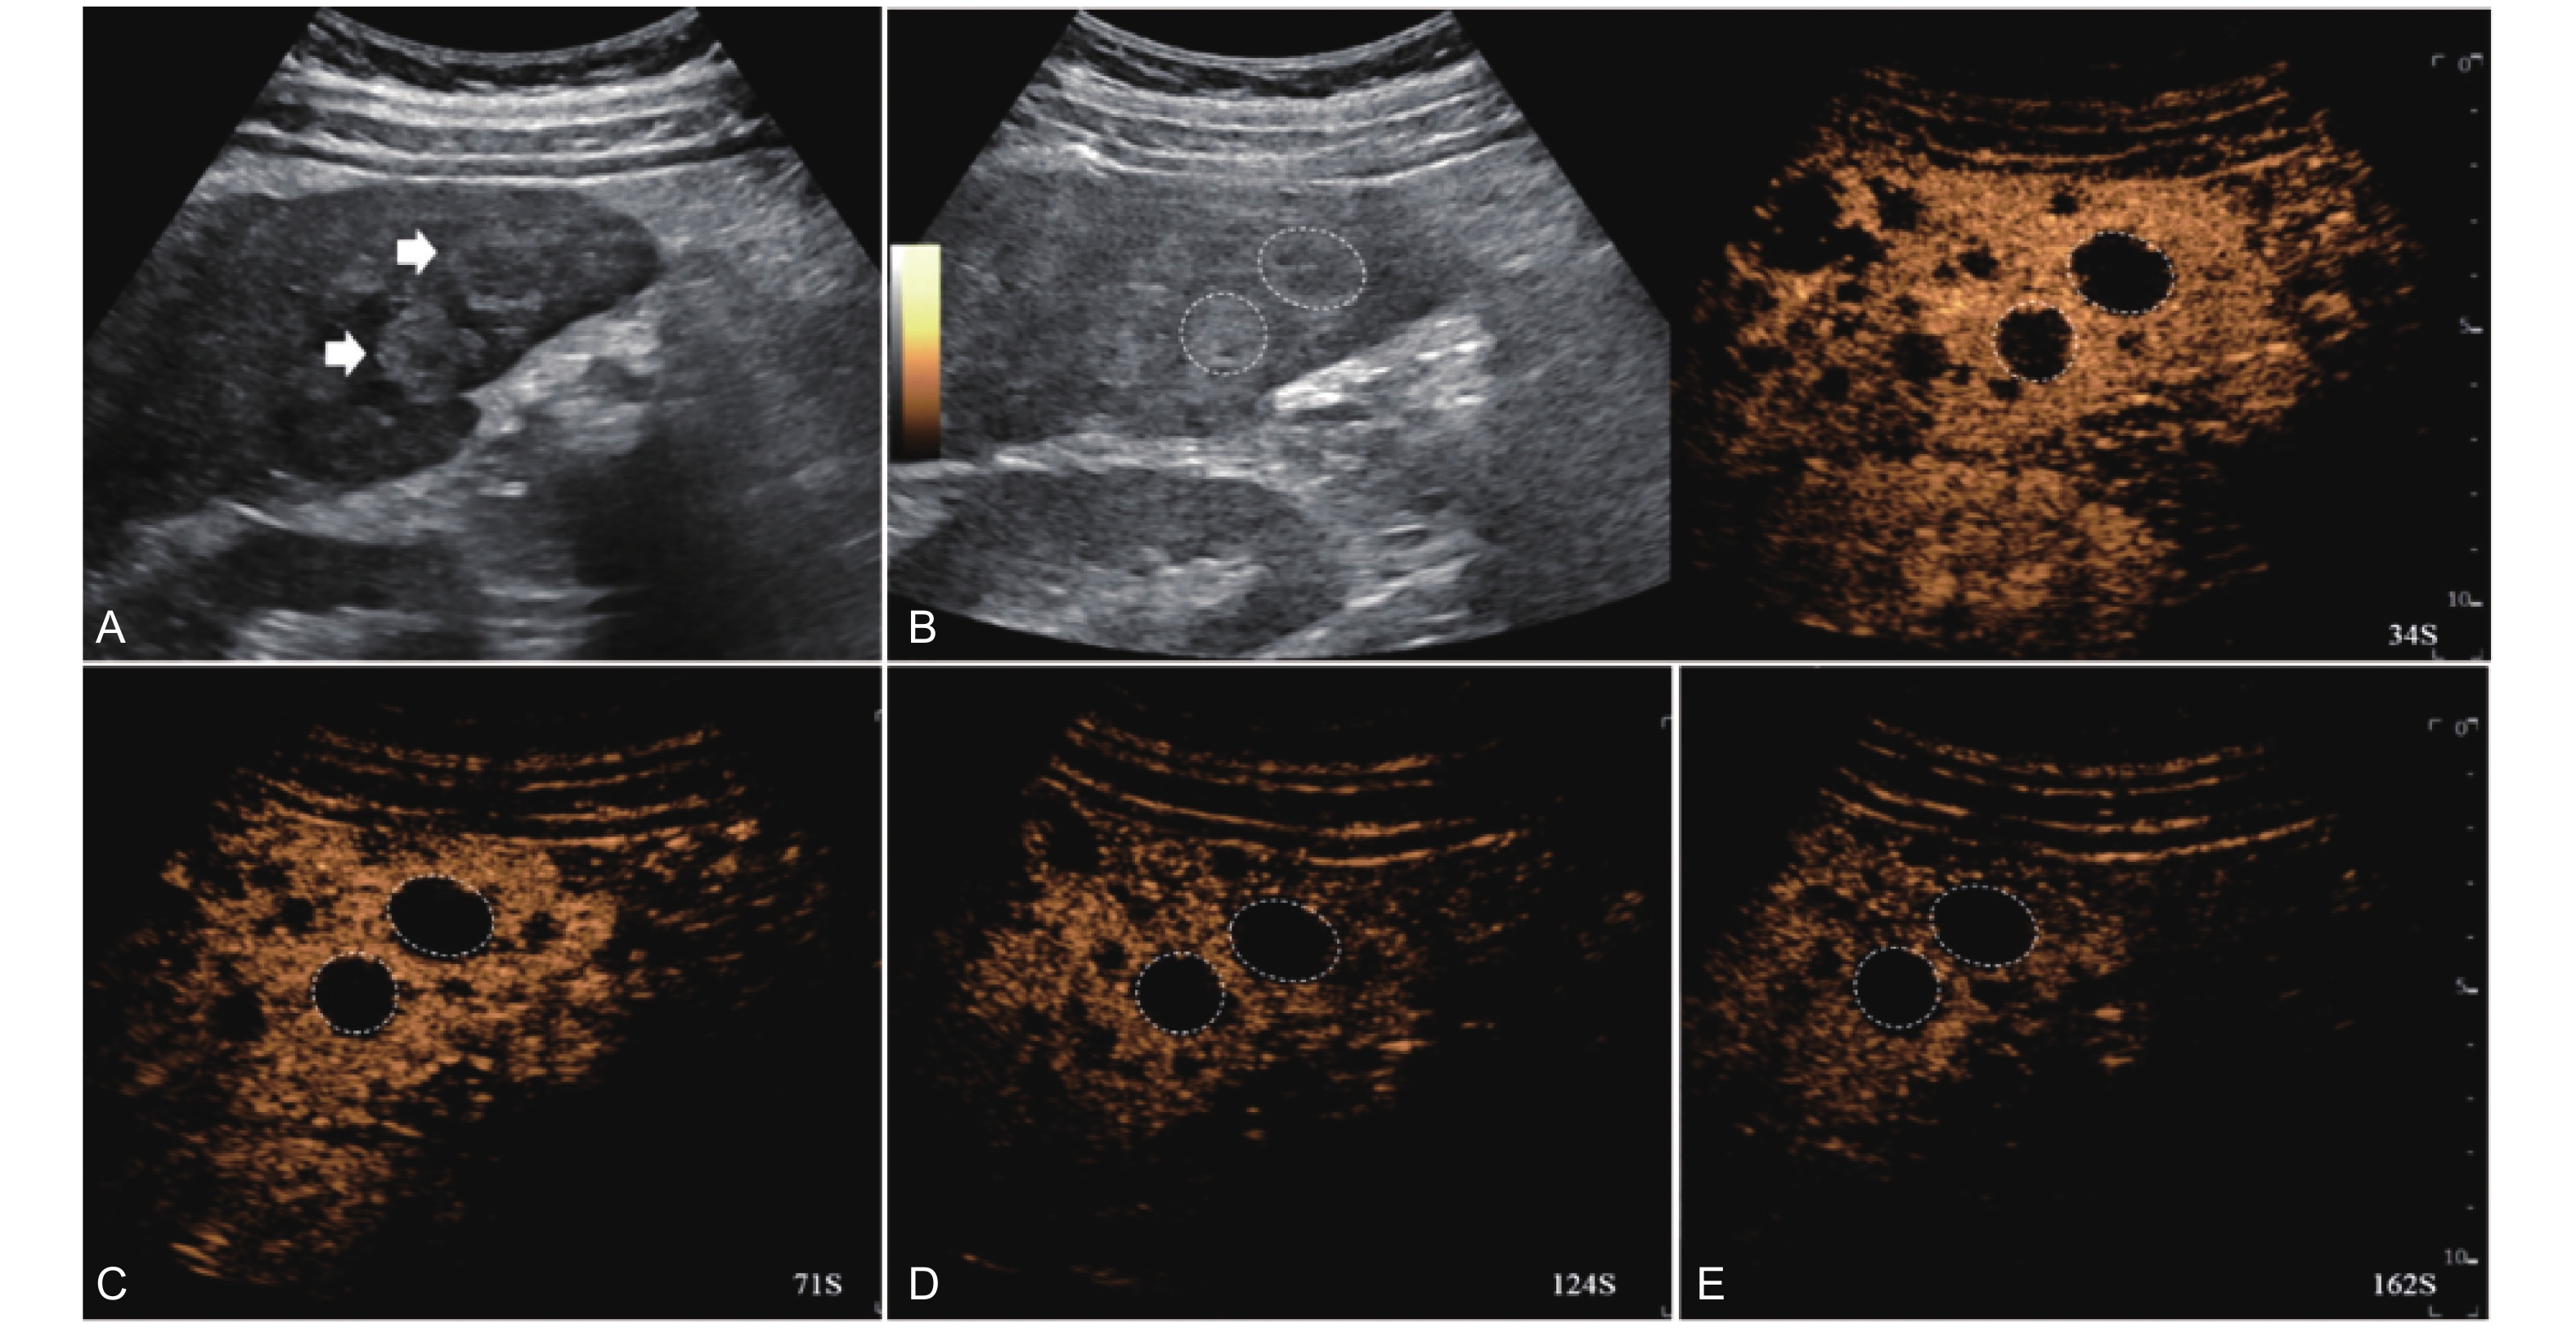

Figure 4

LR-TR Nonviable. Example of a nonviable tumor 14 days after TACE. (A) B-mode image shows two heterogeneous hyperechoic lesions (thick arrow) with irregular shape, measuring 17 mm and 18 mm in segment VI; (B-E) CEUS shows no intralesional enhancement with perilesional enhancement identical to the surrounding liver parenchyma in all phases. Findings are consistent with LR-TR Nonviable."